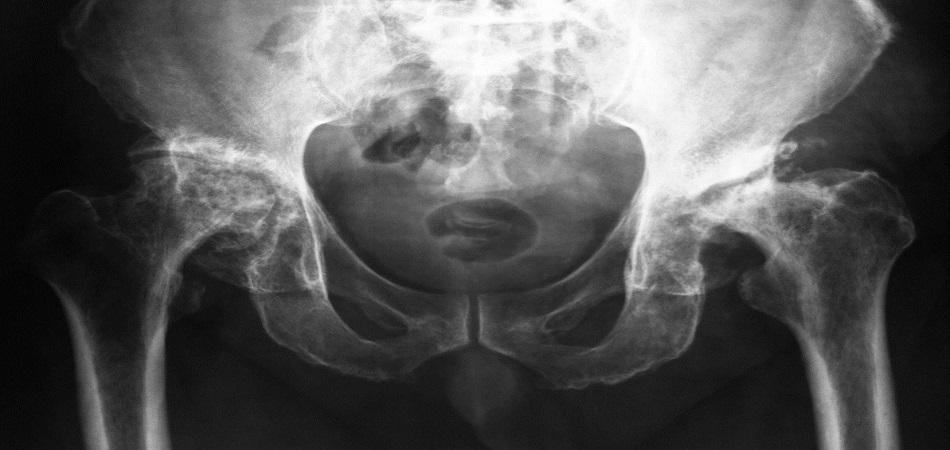

- Рентгенография тазобедренных суставов: Является основным методом подтверждения диагноза. Выполняются снимки в двух проекциях (прямая и аксиальная/Лобстейн-Дюнн) для оценки степени смещения эпифиза головки бедренной кости относительно шейки. Рентгенография позволяет классифицировать эпифизеолиз по степени тяжести (лёгкий, средний, тяжёлый) и типу смещения (стабильный или нестабильный).